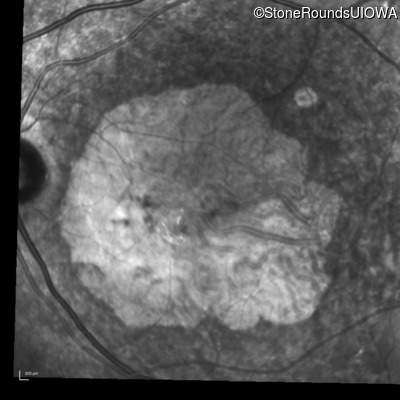

Infrared Fundus Photograph - Right - 20/200 sc

Exemplar

Infrared Fundus Photograph - Left - 20/200 sc